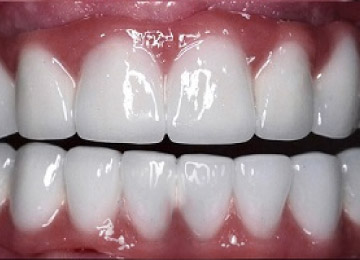

Имплантация зубов: фото «До» и «После»

Фото ДО

Фото ПОСЛЕ

Наведите для просмотра